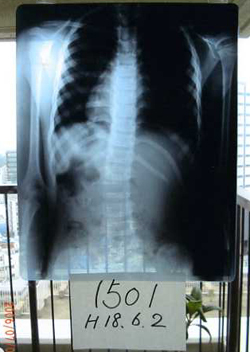

症例5)

初診15度体操6ヶ月で脊柱ほぼ真っ直ぐ、肋骨、両肩のバランスが改善。

小学1年 6歳 女子 学校検診で発見

2006年6月 2日 整形外科へ受診、15度軽い脊柱側湾症ありと診断12月に再診。

2006年6月23日 レントゲンを持参され当院へ。

低度数のため大塚式鍛錬体操を指導し、自宅で毎日していただくことをお願いした。

2006年12月18日 整形外科へ再検診0度とのこと。

2007年 1月 6日にレントゲンを持参され来院された。

左腰椎側湾が見事に改善され肋骨の傾きもなくなり脊柱も真っ直ぐになっています。

本日で大塚整体治療院通院終了とした。

自宅での体操の継続をお願いしました。

2006年6月2日

2006年12月18日

鍛錬体操

6ヶ月後

15度

0度

症例4)は右側湾ですが、この女子は左腰椎型です。

早期の発見体操で改善実例です。このように大塚式鍛錬体操は右、左の湾曲でも効果を発揮します。

低年齢でも

できる体操という証明

でもあり改善の証明です